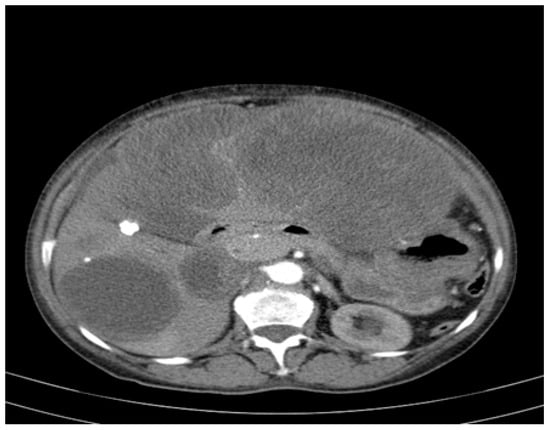

- Largest transonic formation: Located in the left abdomen with a heterogeneous circumferential wall (up to 8.3 in thickness); contained heterogeneous fluid with multiple echogenic/hyperechoic echoes, which were mobile upon compression (Figure 2).

Figure 2. CT appearance at the time of diagnosis: the inferior pole of the cystic formation in the left hepatic lobe extended into the pelvis (14/18/18.5 cm), displacing the transverse colon and small intestine posteriorly toward the right iliac fossa. (a) upper abdomen section on the left (b) pelvic section on the right.